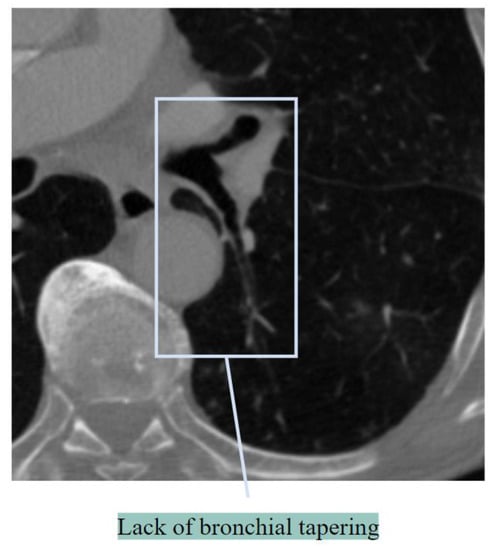

Lack of Bronchial Tapering

Lack of tapering refers to a lack of change in the airway diameter by 2 cm [24]. This results in an increased BA ratio. Figure 4 illustrates a lack of tapering.

Figure 4. Lack of bronchial tapering.